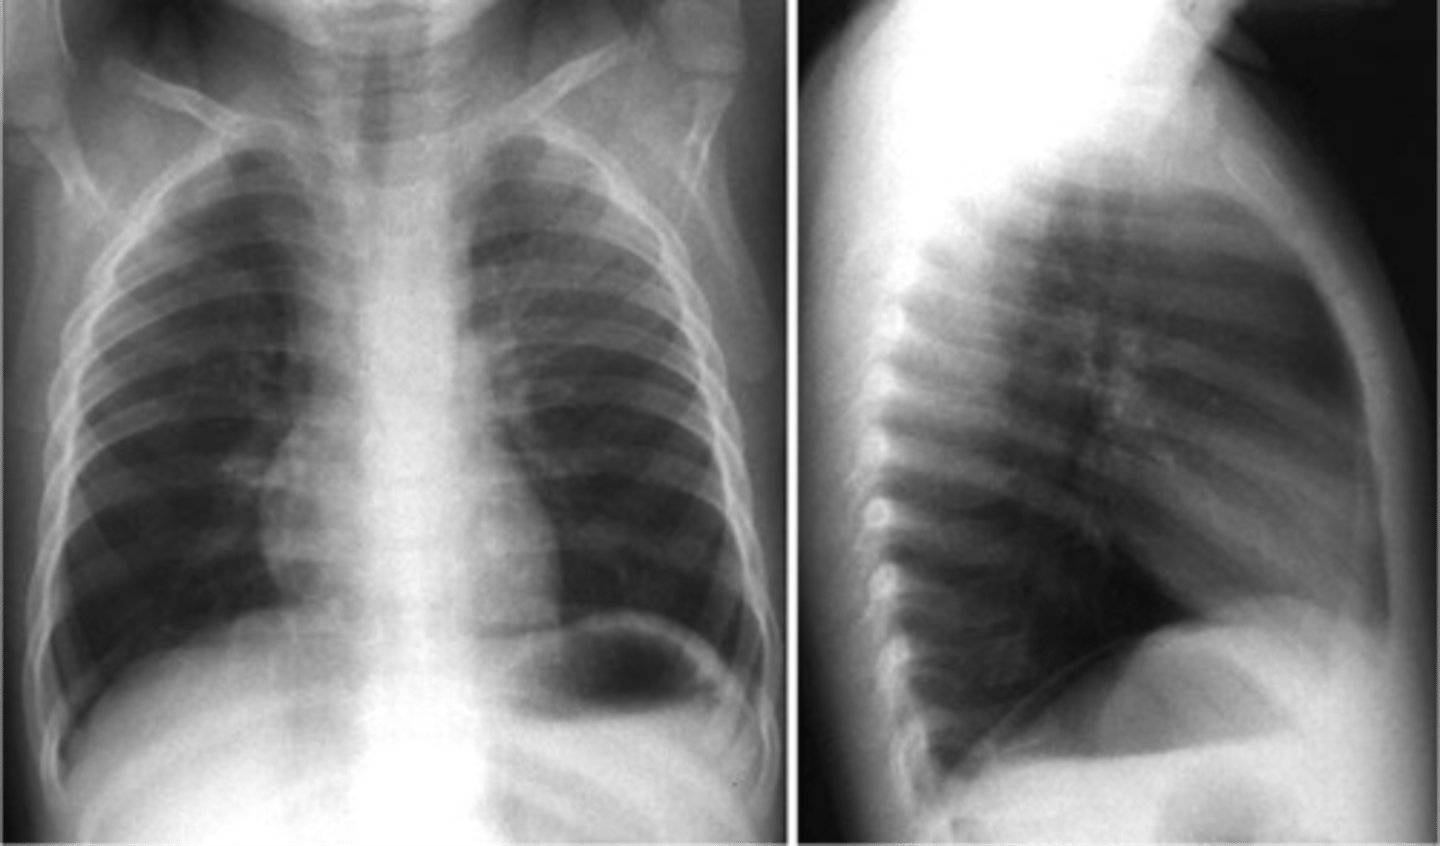

Bronchiectasis

knowt flashcard image

Tram track lines